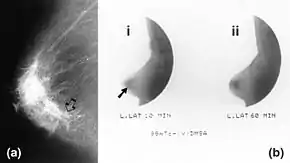

Mammography (left) and DMSA scintimammography (right) images of 4.5cm breast carcinoma